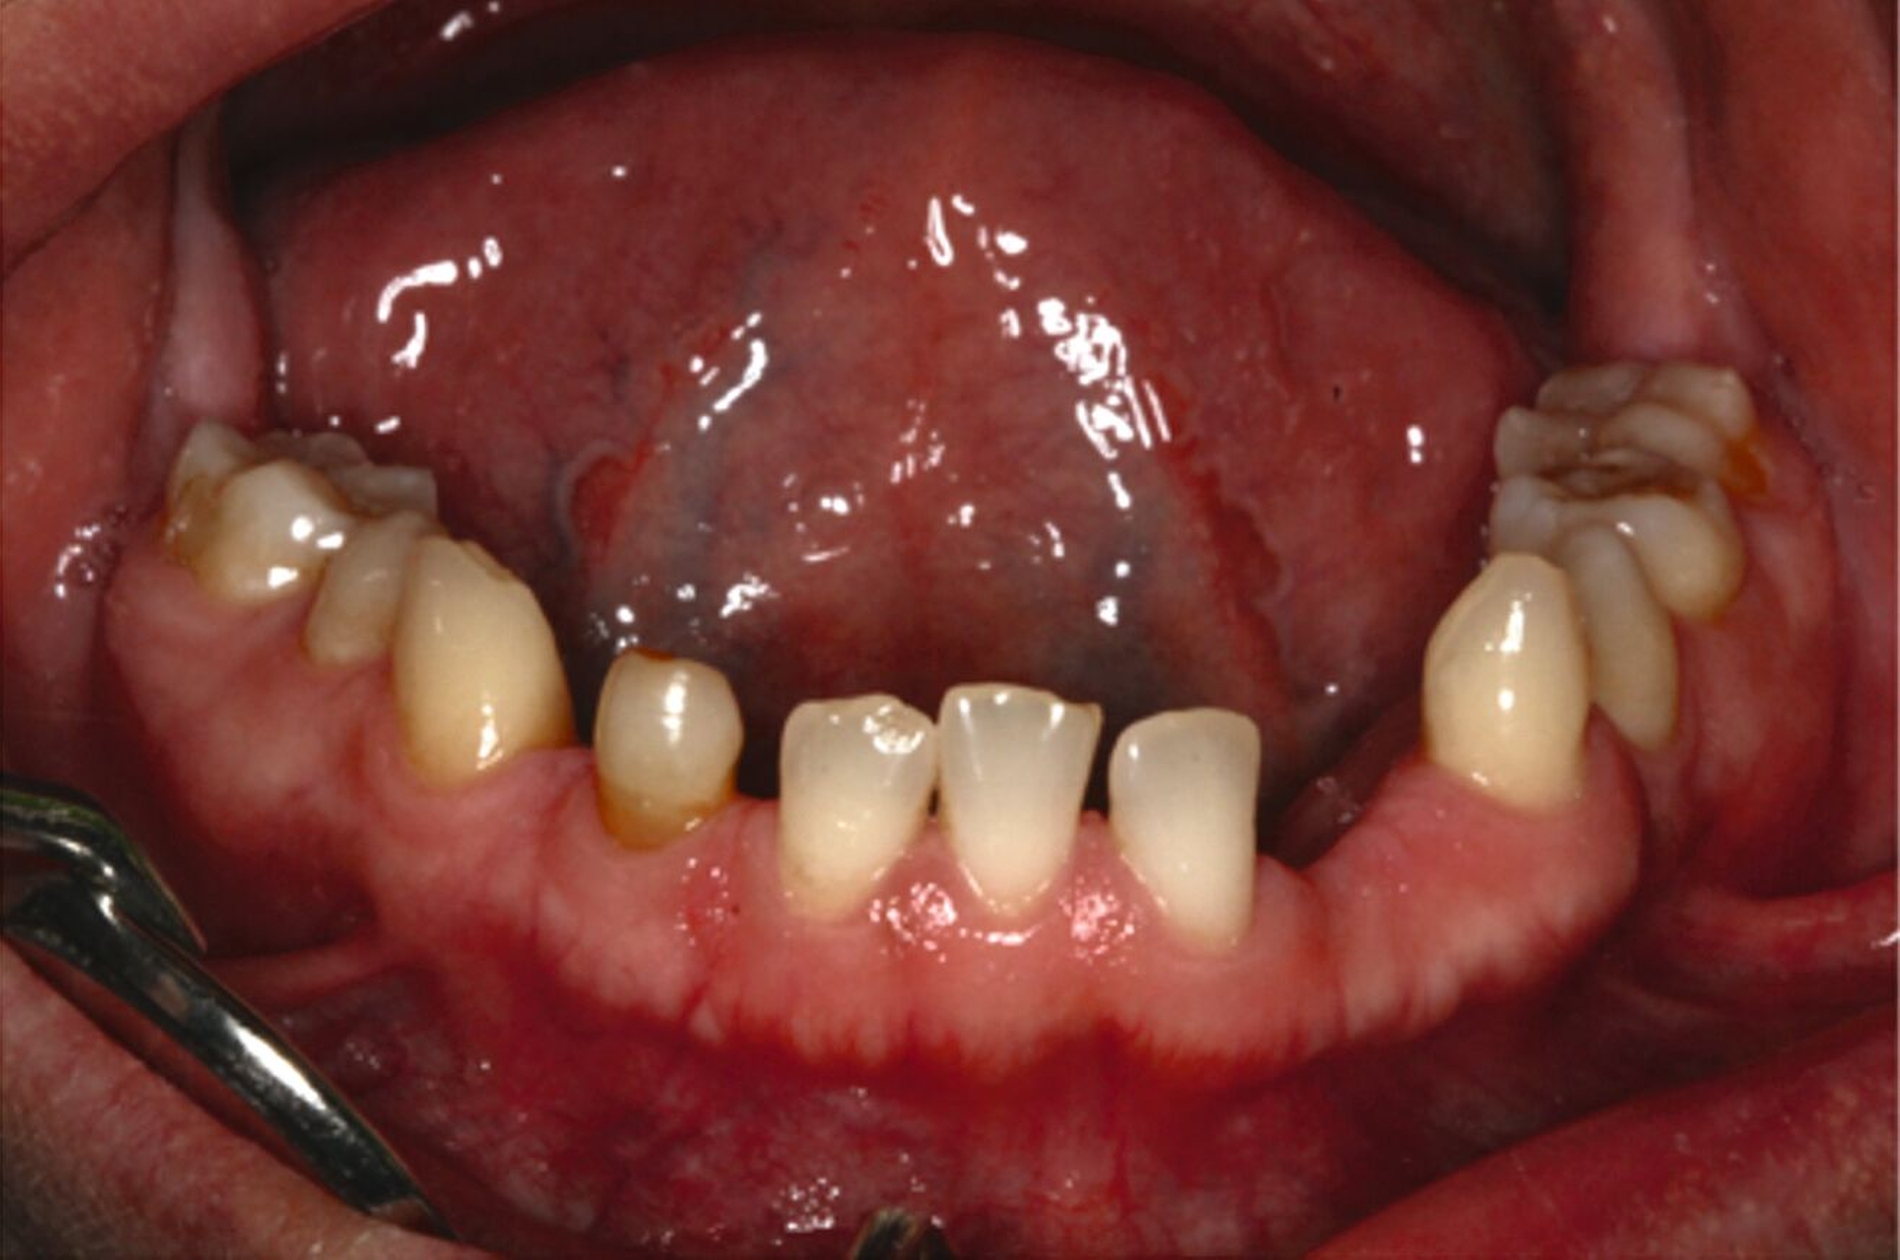

Ein 30-jähriger Patient stellte sich mit multipler Oligodontie (15 fehlende bleibende Zähne), Persistenz von Milchzähnen sowie ausgeprägter Dysgnathie mit progenem Deckbiss vor. Klinisch zeigten sich hypoplastische Restzähne, Fehlstellungen und erhebliche funktionelle Beeinträchtigungen (Abbildung 1). Sein Wunsch bestand in einer möglichst optimalen ästhetischen und funktionellen Versorgung seiner für ihn äußerst unbefriedigenden Gebisssituation. Die molekulargenetische Analyse bestätigte eine homozygote Mutation im WNT10A-Gen als Ursache der Zahnagenesie.